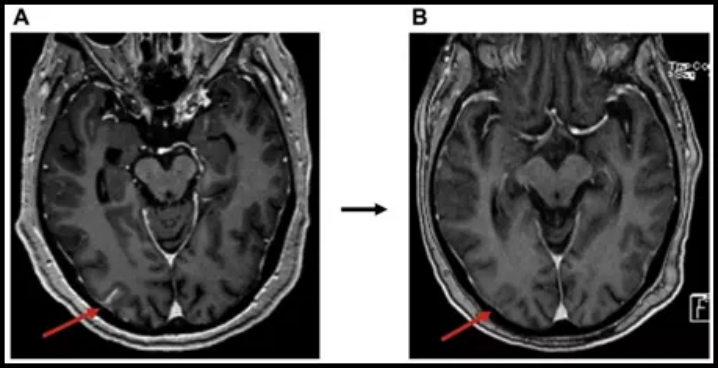

一般从80mg/天→160mg/天适用于无可针对新靶点,通过增加体内药物浓度杀伤肿瘤,特别是脑软膜转移的患者。BLOOM试验纳入了21例EGFR19/21突变的软脑膜转移患者(既往中位治疗线数=3,都用过EGFR靶药),使用奥希替尼160mg/天治疗。其中T790M突变共8例。结果显示,经确认的软脑膜ORR为33.33%,DCR达到76.19%。这里举一个案例。下图A及B为奥希替尼增量(80mg→160mg)前后脑软膜的病灶变化,加大剂量后病灶疗效达到部分缓解PR。 6.“脉冲式”特罗凯: